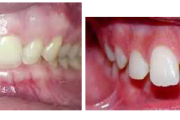

Turritavad ülemised lõikehambad.

ettepoole ulatuvad ülahambad